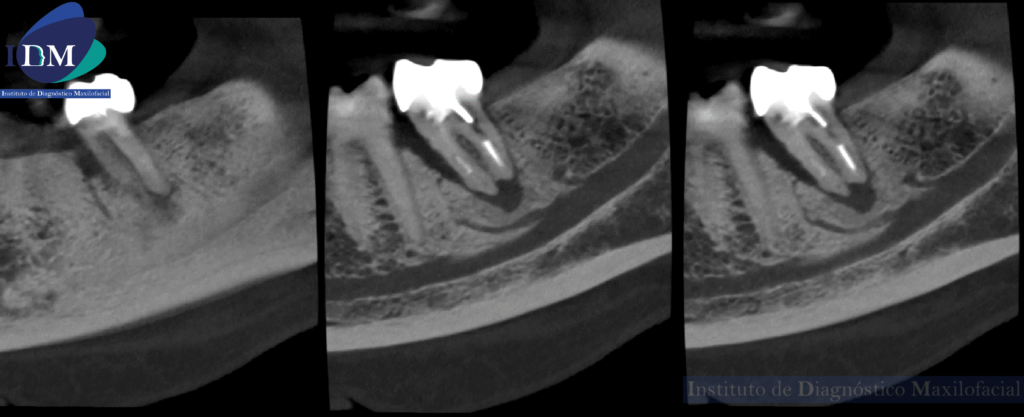

Así mismo se evidencia en la tomografía localizada una variante anatómica por parte del conducto dentario inferior. Donde se visualizada dos ramos accesorios del tronco principal sin confluencia.

CORTES TANGENCIALES